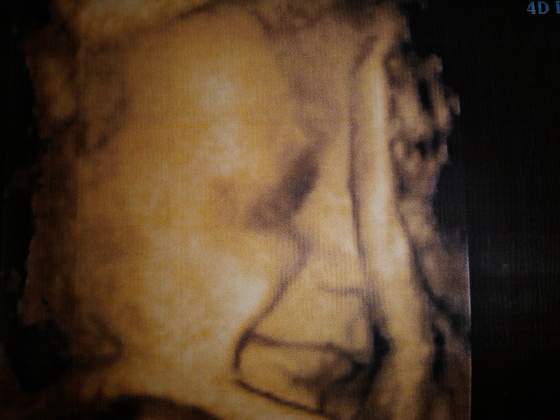

Medluję, że jestem już PO :-)

Otóż moja szyjka ma niecały 1 cm i jest miękka... tak więc w każdej chwili mogę rodzić. Jak tylko poczuję skurcze, mam jechać do szpitala... biorąc pod uwagę pój pierwszy szybki poród.

Gin nie kazała już brać nospy. Generalnie mam się już psychicznie nastawić, że to może być zaraz